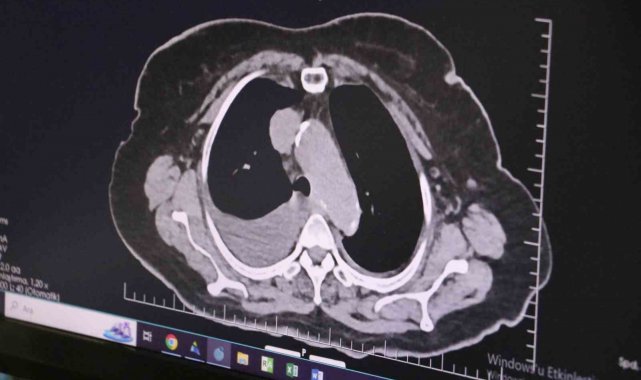

Ünlü sanatçı Volkan Konak'ın ani vefatı sonrasında toplumun kalp sağlığına dair daha çok düşünmeye başladığını belirten Dr. Erdoğu, "Gençler ne yazık ki sağlıksız bir sürece doğru gidiyor. Kendilerine zaman ayırmaları, ulaşılabilir hedefler koymaları ve kendilerini bulmalarını tavsiye ediyorum. Yakın zamanda sevdiğimiz, keyifle dinlediğimiz ve dilimize dolanan türküleri ile meşhur olan Volkan Konak'ı kaybettik. Volkan Konak'ın ölümünden sonra, bizim de düşündüğümüz ve toplumun gündemini oluşturan bir durum gerçekleşti. Toplumsal alanlarda, kalp hastalıkları oluştuğunda veya kalpte durma meydana geldiğinde ne yapılacak, nasıl bir yol izlenecek diye düşünmeye başladık. Böyle bir olay hastanenin içerisinde olması halinde, kalp masajı gibi hızlıca müdahale uygulayabiliyor ve defibrilatör dediğimiz cihazlara çabuk erişim sağlanabiliyor. Böylelikle hayatta kalma ihtimali oldukça yüksek oluyor ve hasta hayata döndürülebiliyor. Ama bu süre uzadıkça ne yazık ki şansımız azalıyor. Örneğin okulları, büyük bir fabrikayı, belediyeyi, itfaiyeyi düşünelim. İnsanların bir arada bulunduğu ve organize olduğu yerlerde, bu insanlara acil kalp masajı eğitiminin verilmesi büyük önem arz etmektedir. Çevresinde ciddi kalp yetersizliği olan, bypass olmuş insanların yakınlarının dahi, kalp durması konusunda eğitim alması ve kalp masajını bilmeleri gerekiyor. Çok kalabalık insanların çalıştığı ofis ve okul gibi alanlarda defibrilatör dediğimiz kalbi şoklayarak çalıştıracak cihazların bulunması gerekiyor. Bu tür cihazların ve ani hayati müdahale eğitimlerinin insanlara verilmesi büyük önem taşımaktadır" diye konuştu.